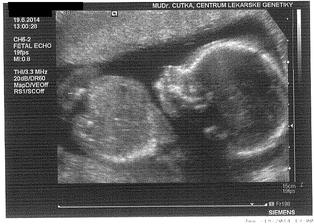

* 19.6.2014 - UZ v genetickém centru ve 20.tt - miminko je ukázkové - 25cm, 290g a odpovídá poslední MS. a máme potvrzenou holku 🙂 Je nádherná a máme i krásné video 🙂